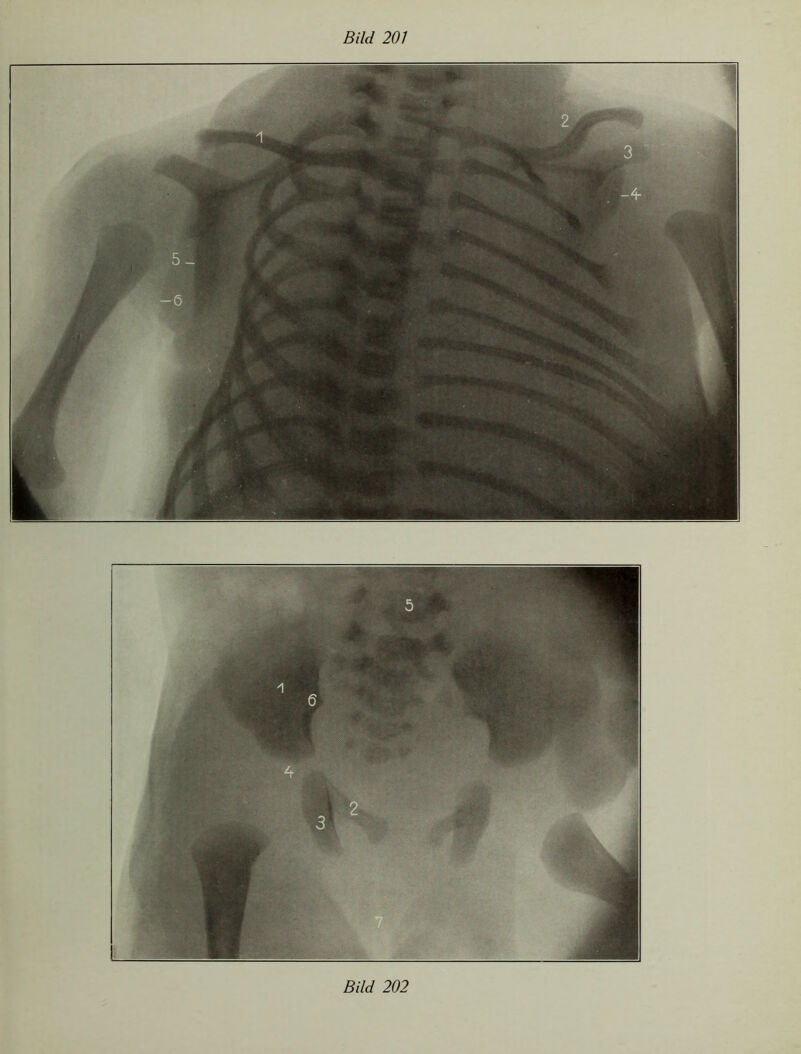

Atlas typischer Röntgenbilder vom normalen Menschen : ausgewählt und erklärt nach chirurgisch-praktischen Gesichtspunkten, mit Berücksichtigung der Varietäten und Fehlerquellen, sowie der Aufnahmetechnik / von Rudolf Grashey.

Credit: Atlas typischer Röntgenbilder vom normalen Menschen : ausgewählt und erklärt nach chirurgisch-praktischen Gesichtspunkten, mit Berücksichtigung der Varietäten und Fehlerquellen, sowie der Aufnahmetechnik / von Rudolf Grashey. Source: Wellcome Collection.